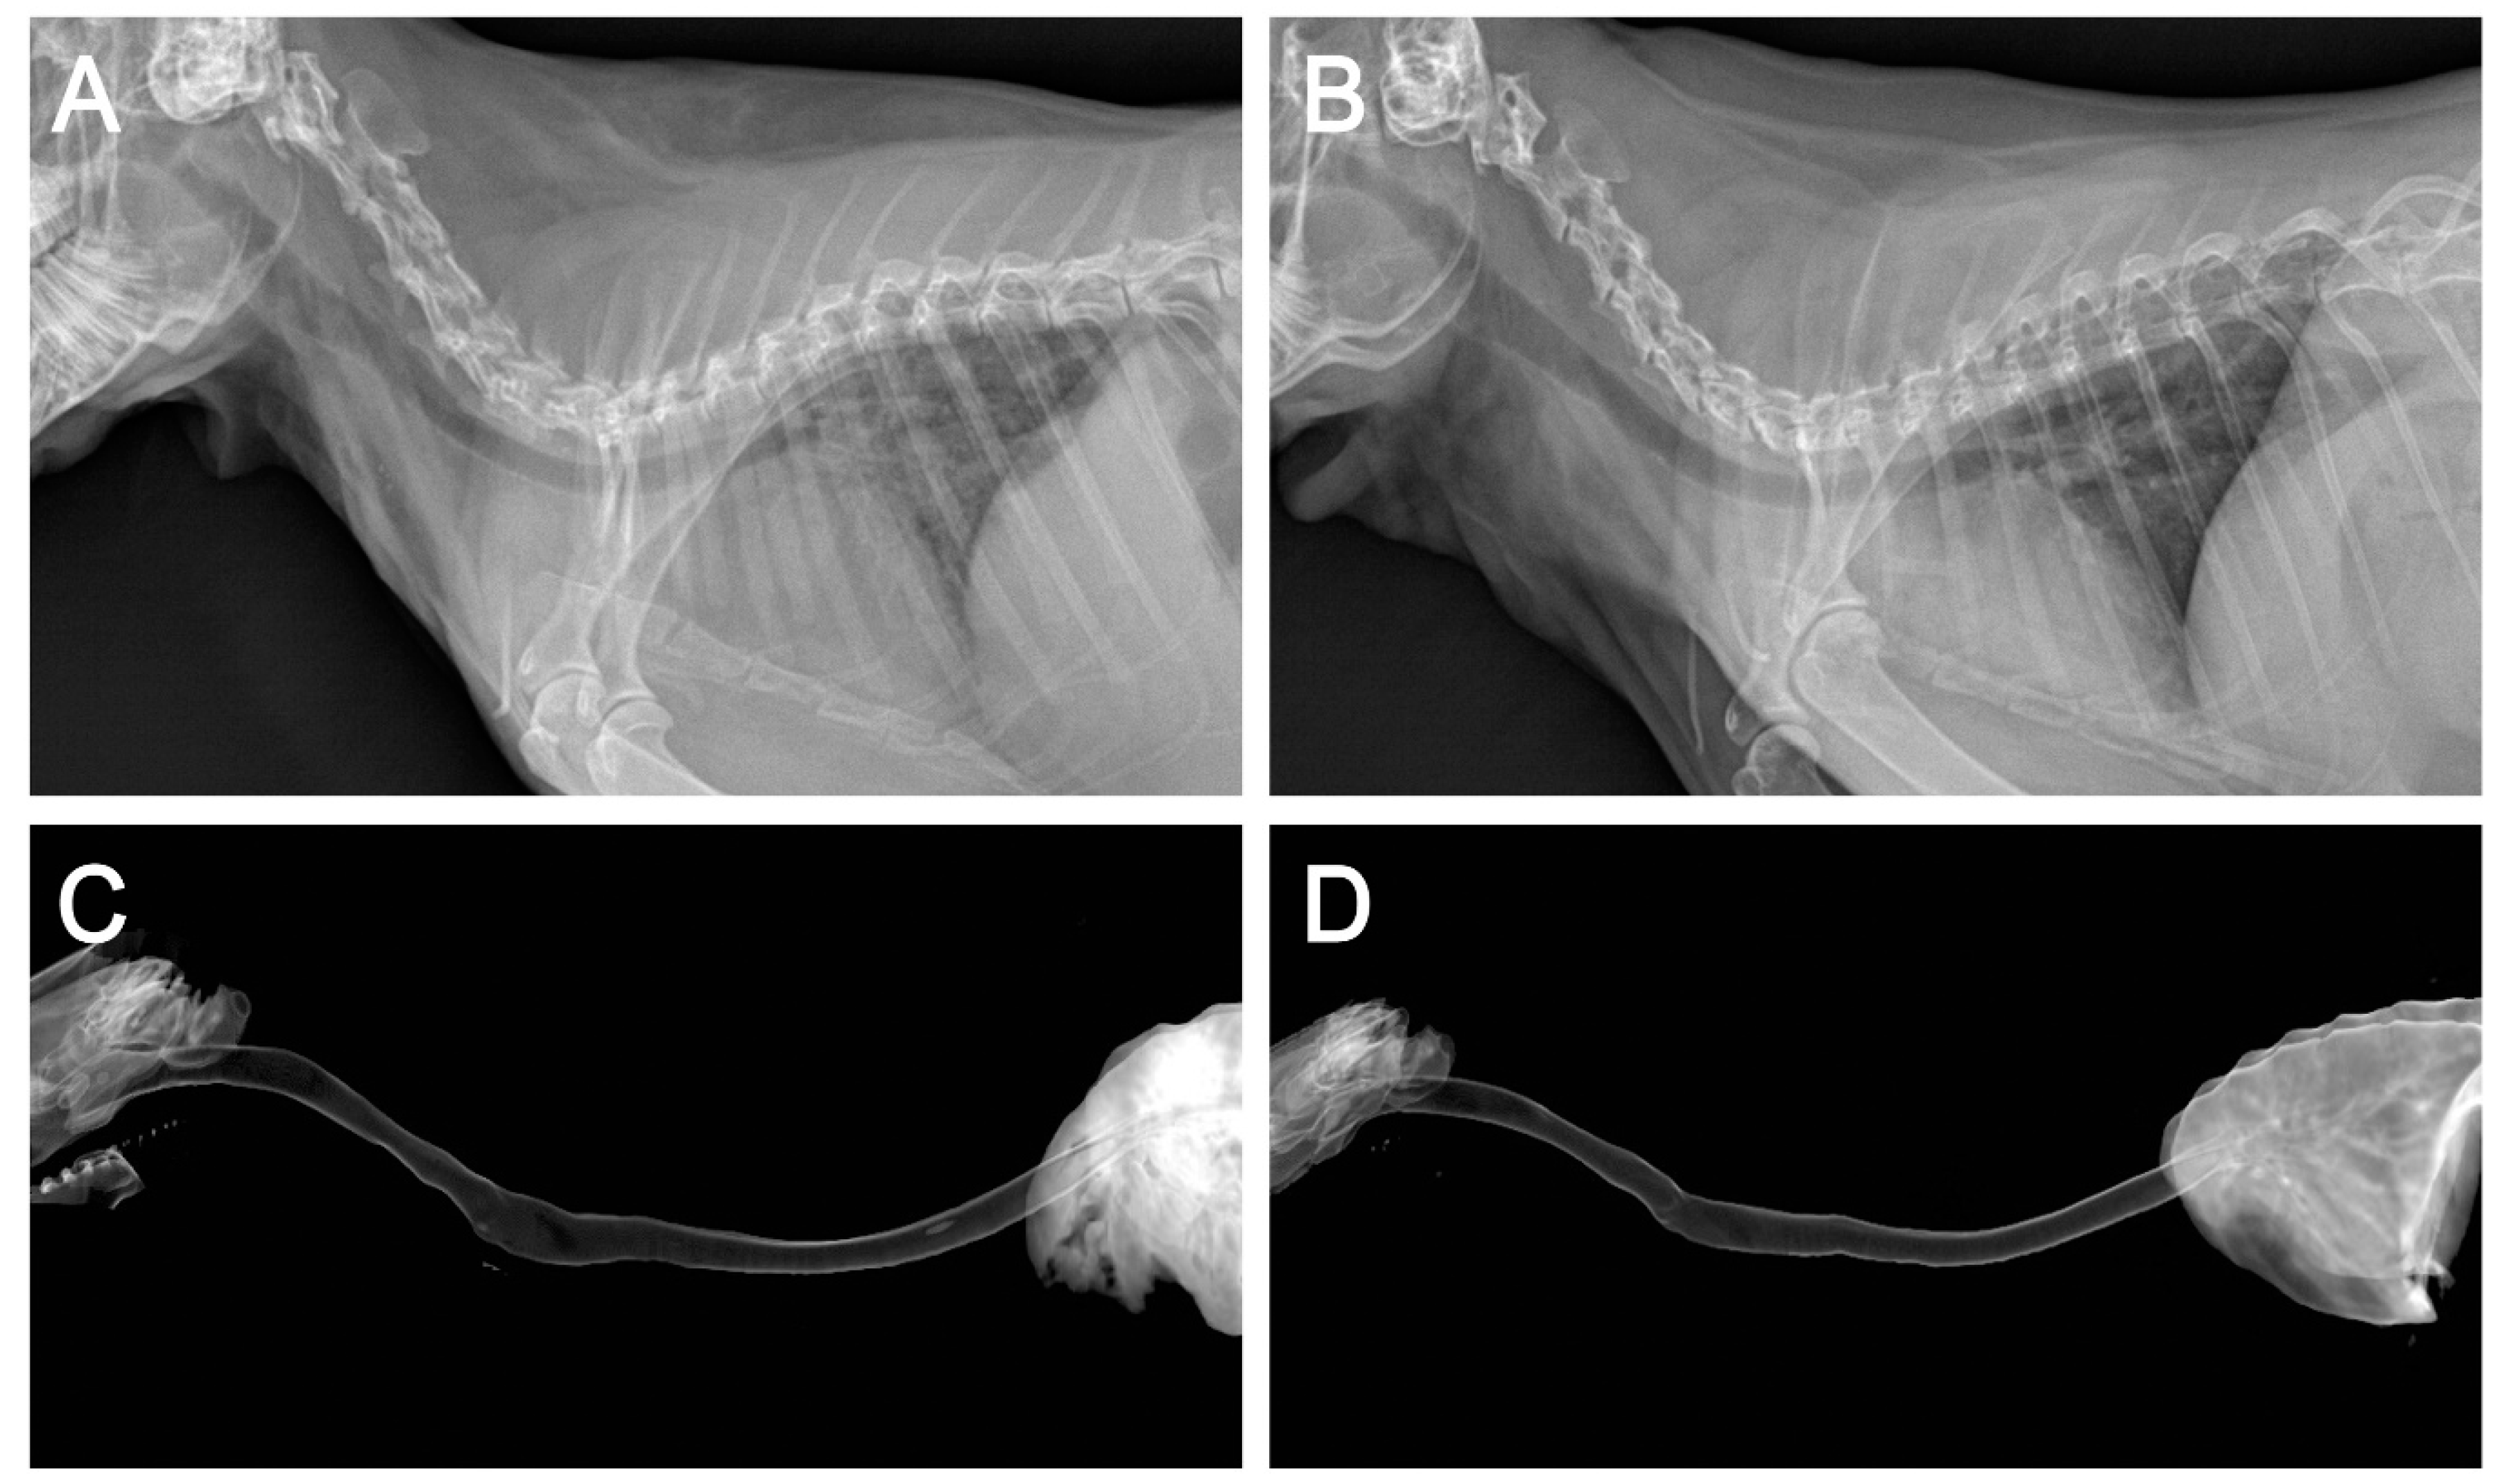

2.4. Application of the 3D Bioprinted Artificial Trachea

2.5. In Vivo Epithelialization and Neo-Cartilage Formation